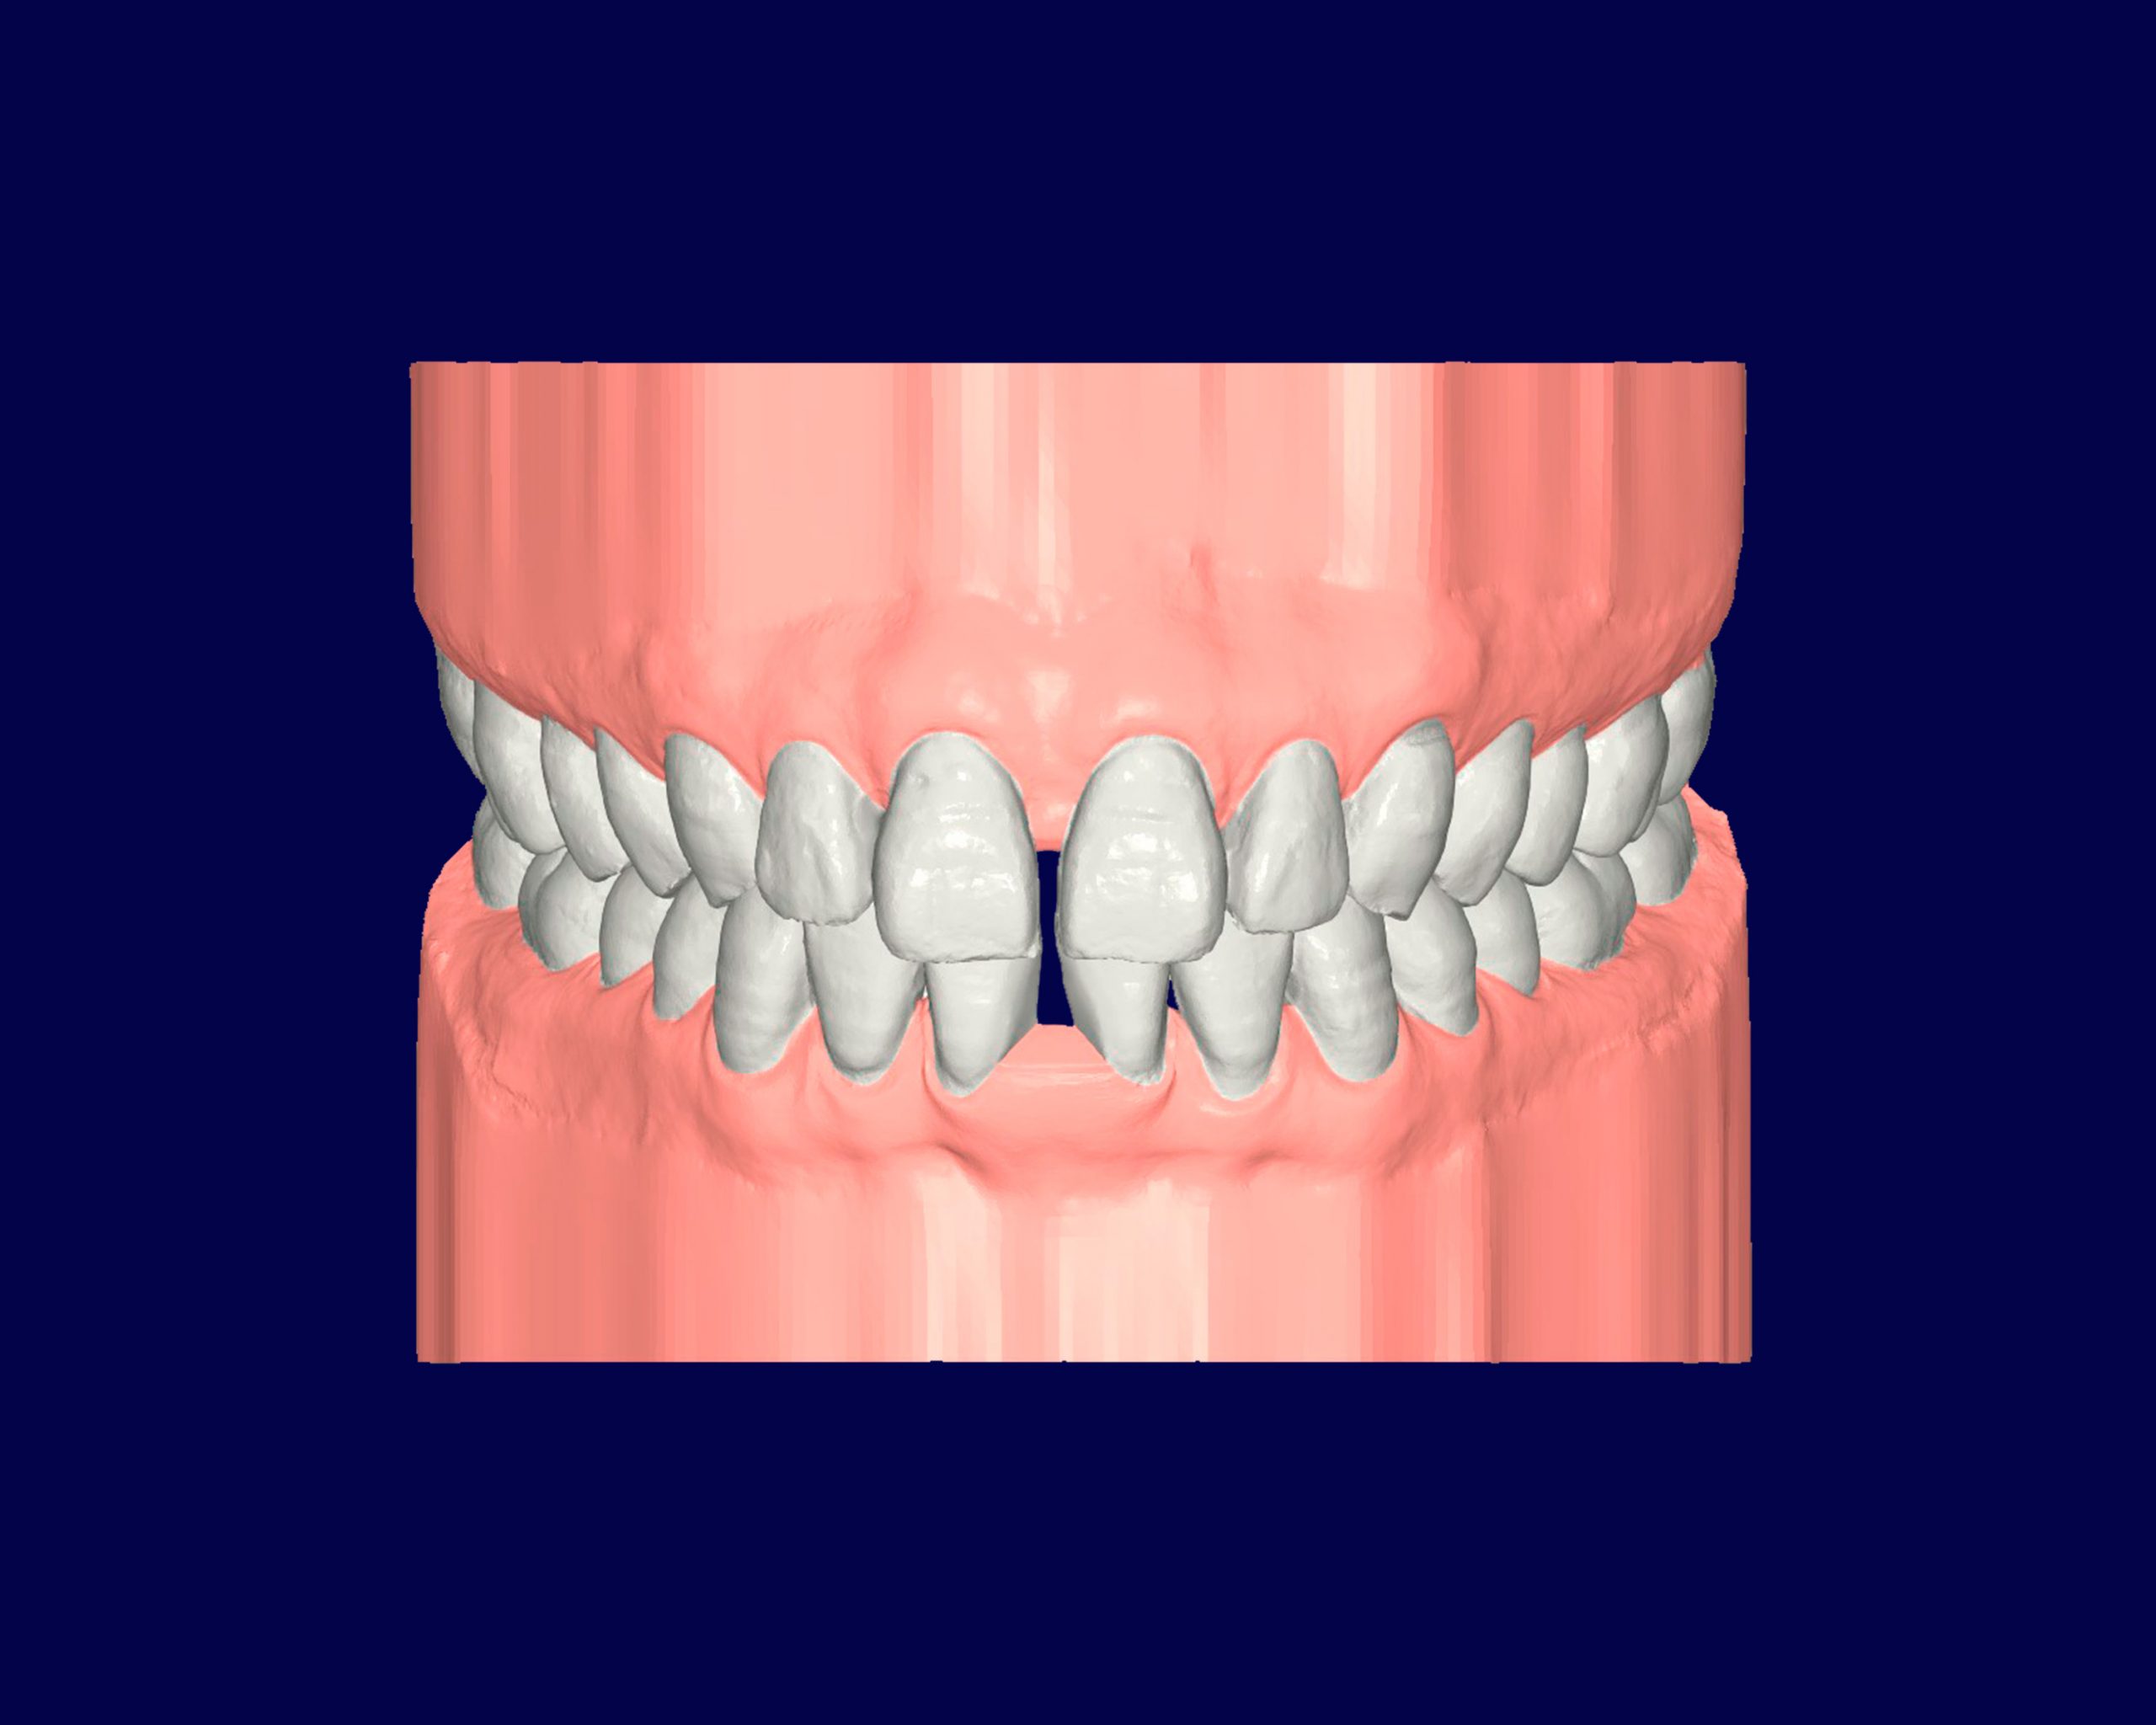

Diastemas

Los diastemas son espacios o huecos anormales entre dos dientes, comúnmente entre los dientes frontales superiores.

Aunque a menudo son una cuestión estética, pueden también estar relacionados con problemas funcionales si afectan la mordida o la alineación dental.

INITIAL

22 Semanas de Tratamiento